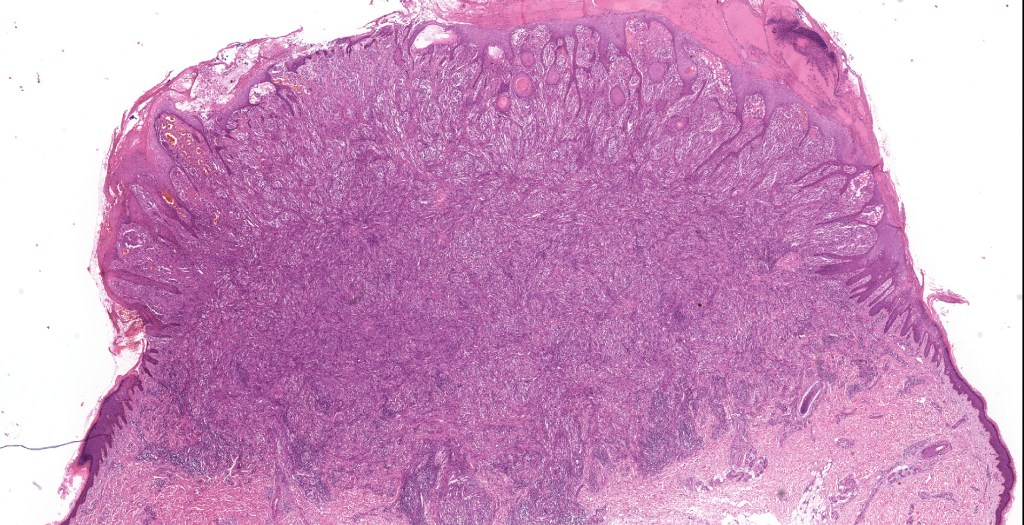

•Sharply circumscribed (begins and ends with a nest), symmetrical dome-shaped lesion. Symmetry is both horizontal and vertical (see image below)

•Wedge-shaped with the base uppermost or sometimes plaque-shaped silhouette

•Matures with depth-often best recognized at scanning/low power magnification & readily confirmed with S100 or MART1

•Hyperkeratosis & acanthosis, sometimes very marked

•Superficial vascular ectasia very frequently present